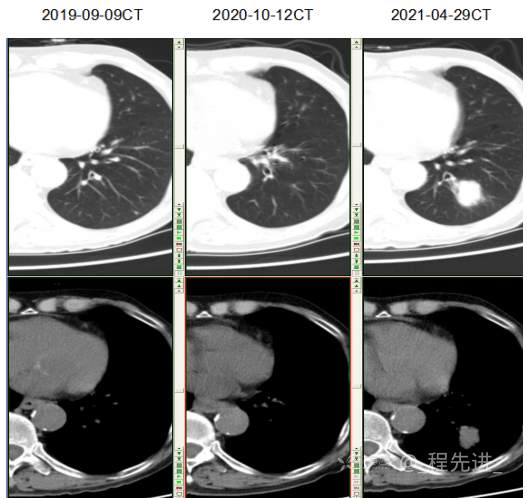

主诉: 反复咳嗽、咳痰10余年,加重10余天

现病史:患者10年前开始出现反复咳嗽、咳痰,3年前出现活动性气喘,休息后症状可缓解;冬春季节或受凉后症状加重,不伴反复下肢浮肿,曾在我院住院诊断为”慢性阻塞性肺疾病”,给予解痉平喘、化痰、输氧治疗有效,平素生活能自理,不能从事体力劳作,此次发病于10天前可能受凉后咳嗽、咳痰加重,咳黄痰,呈阵咳,咳白痰,活动气喘加重,不伴畏寒、发热,无胸痛,今来我院就诊,拟“慢性阻塞性肺病伴急性加重”收住入院,自发病以来,患者精神、食纳、睡眠一般,大小便如常,体重有下降,县体不详。患者及陪护人员:否认14天内离开过南丰,否认14天内有新型冠状病毒感染病例报告社区或中高风险地区的旅行史或居住史,否认14天内与新型冠状病毒感染的患者或无症状感染者有接触史,否认14天内曾接触过来自有病例报告社区或中高风险地区的发热或有呼吸道症状的患者,否认14天内在小范围如家庭、办公室、学校班级等场所,出现5例及以上发热和/或呼吸道症状的聚集性发病病例。

既往史:平素健康状况 一般,有胃大部分切除病史40年,去年10月复查胃镜提示吻合口溃疡;肠镜检查多发性结肠息肉。因胸闷、气促去年在心血管科住院,行冠脉造影检查,提示有冠状动脉粥样硬化,但未行支架植入。有前列腺增生病史数年,目前一直口服非那雄胺、盐酸坦索罗辛治疗,有痛风病史数年,未正规治疗,近1年来出现记忆力明显下降、下肢无力症状。否认病毒性肝炎、肺结核、伤寒、疟疾病史否认高血压、糖尿病、高血脂病史 ,否认脑血管疾病史无 静脉血栓栓塞个人史, 否认外伤、中毒, 有胃大切手术史,有腰椎压缩性骨折行手术治疗 , 否认输血史,无药物过敏史,无食物过敏史,预防接种史 不详。